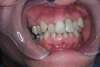

5 - Facettes dentaires et chevauchement - Paris 16

Ces cas cliniques sont une illustration pédagogique de traitements odontologiques. L'objectif de ceux ci est de mettre en image des soins dentaires pour une meilleurecompréhension de ceux ci.